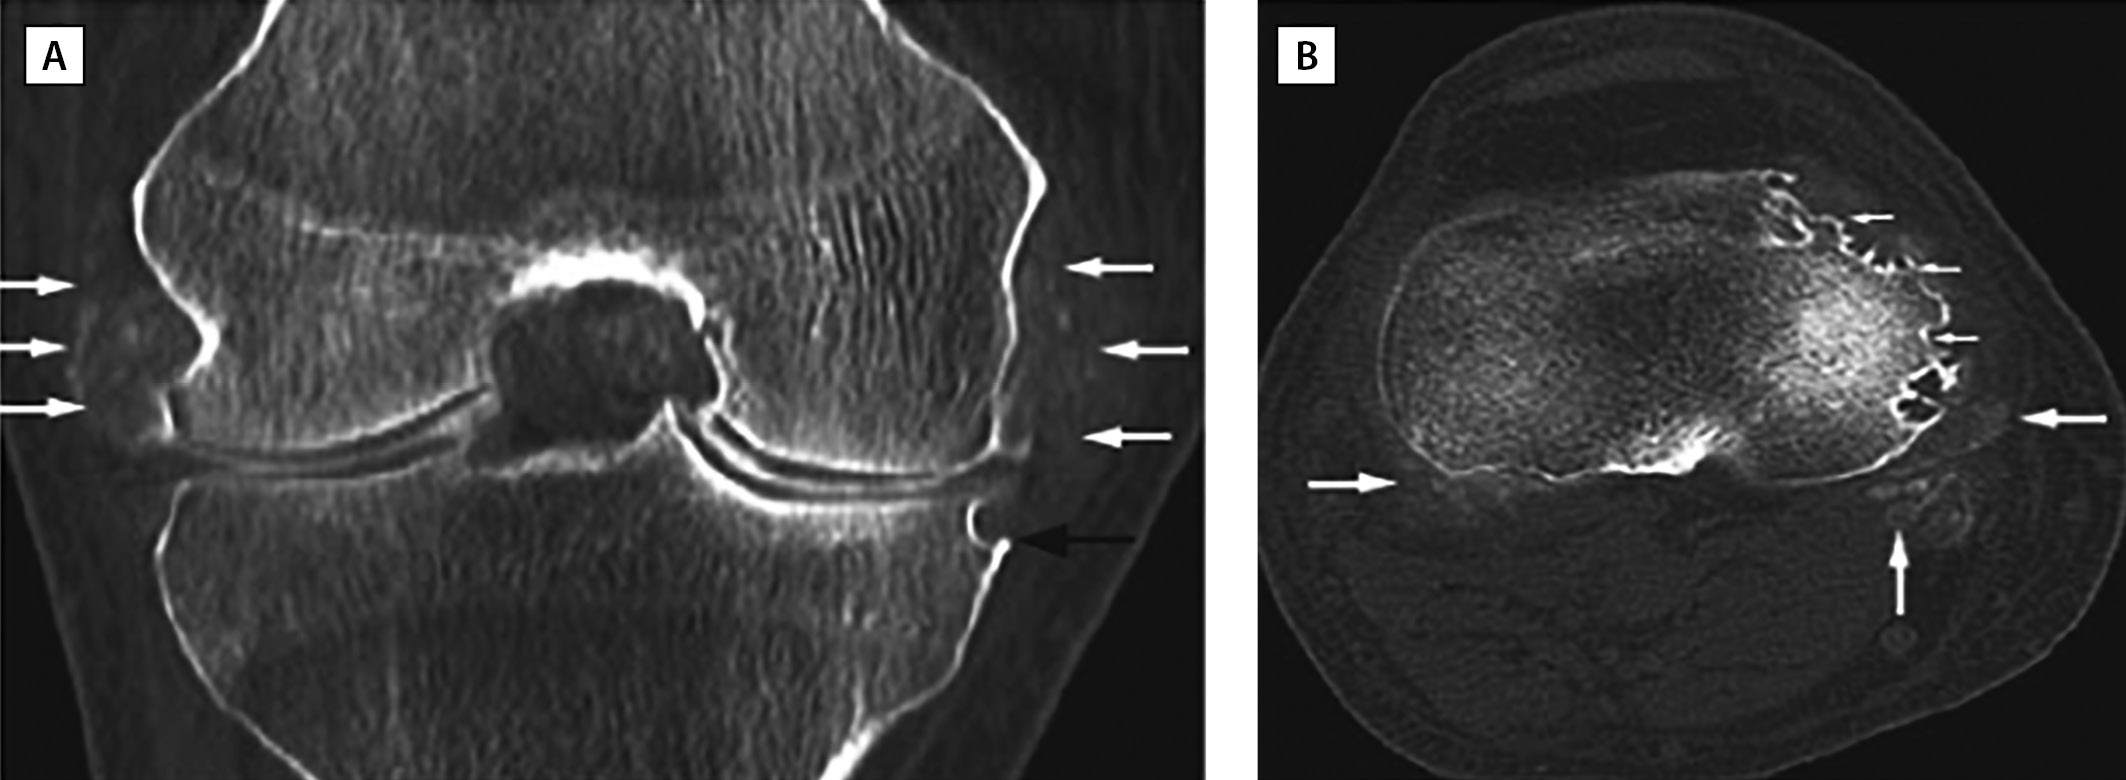

Например, S. Chatterjee и соавт. [64] описали клинический случай пациента 67 лет, страдающего хронической тофусной подагрой более 30 лет. На момент осмотра пациент предъявлял жалобы на артрит правого коленного сустава с типичными для подагры характеристиками. Назначенная 6 мес назад УСТ (аллопуринол 100 мг/сут) не привела к нормоурикемии (МК сыворотки — 410 мкмоль/л). Однако увеличение дозы препарата до 200 мг/сут в отдаленной перспективе способствовало не только снижению частоты и интенсивности приступов, но и рассасыванию, в том числе, «внутрикостных» тофусов, обнаруженных на КТ, проявляющемуся в уменьшении числа и размеров костных эрозий (рис. 2, 3).

Рисунок 3. КТ правого коленного сустава пациента с хронической тофусной подагрой через 3 года после обращения (адаптировано из Chatterjee S. и соавт., 2008) [64].

(A) Разрешение тофусов; уменьшение эрозии медиального мыщелка большеберцовой кости.

(B) Полное разрешение тофусов и частичное заживление эрозий (стрелки).

Figure 3. CT scan of the right knee of a patient with chronic tophi gout 3 years after presentation (adapted from Chatterjee S. et al., 2008) [64].

(A) Resolution of tophi; reduced erosion of the medial tibial condyle.

(B) Complete resolution of tophi and partial healing of erosions (arrows).

Таким образом, тофусное поражение костной структуры является обратимым. Применение УСТ, в частности ингибиторов ксантиноксидазы (аллопуринола и фебуксостата), способствует снижению продукции АФК, потенцирующих резорбцию костной ткани, приводит к рассасыванию отложений кристаллов МУН, купированию микрокристаллического воспаления и индукции остеобластогенеза, что способствует репарации костной ткани. Клиническое значение этого феномена позволяет считать УСТ протективной при поражении костной ткани у пациентов с подагрой, а возможно, и при бессимптомной ГУ.